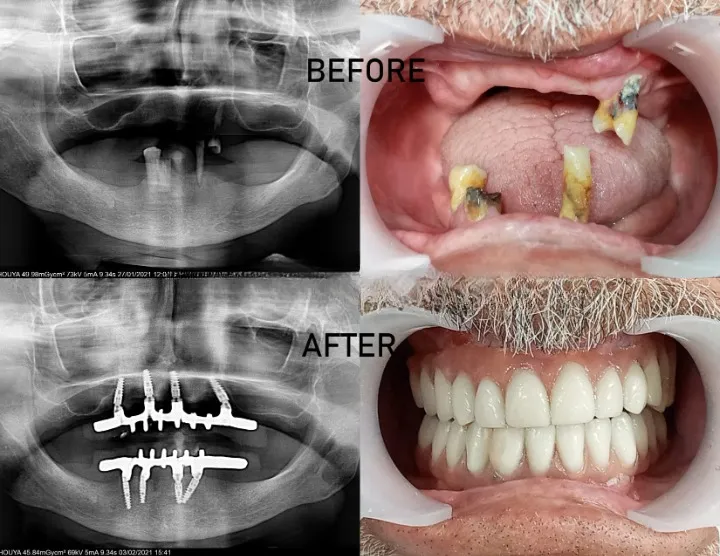

Sauver et préserver vos dents

avec expertise spécialisée

Le déchaussement dentaire et les maladies parodontales représentent la première cause de perte de dents chez l'adulte, mais ce n'est pas une fatalité. À Agdal Dental Clinic, notre expertise en parodontologie avancée vous offre des solutions thérapeutiques de pointe pour stopper l'évolution de ces pathologies et régénérer les tissus perdus. Grâce à des techniques microscopiques, des thérapies laser et des protocoles régénératifs, nous sauvons vos dents naturelles et restaurons la santé gingivale durablement.